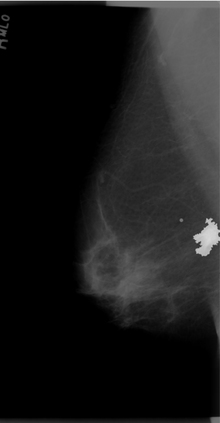

Breast cancer is the most widespread neoplasm among women and early detection of this disease is critical. Deep learning techniques have become of great interest to improve diagnostic performance. Nonetheless, discriminating between malignant and benign masses from whole mammograms remains challenging due to them being almost identical to an untrained eye and the region of interest (ROI) occupying a minuscule portion of the entire image. In this paper, we propose a framework, parameterized hypercomplex attention maps (PHAM), to overcome these problems. Specifically, we deploy an augmentation step based on computing attention maps. Then, the attention maps are used to condition the classification step by constructing a multi-dimensional input comprised of the original breast cancer image and the corresponding attention map. In this step, a parameterized hypercomplex neural network (PHNN) is employed to perform breast cancer classification. The framework offers two main advantages. First, attention maps provide critical information regarding the ROI and allow the neural model to concentrate on it. Second, the hypercomplex architecture has the ability to model local relations between input dimensions thanks to hypercomplex algebra rules, thus properly exploiting the information provided by the attention map. We demonstrate the efficacy of the proposed framework on both mammography images as well as histopathological ones, surpassing attention-based state-of-the-art networks and the real-valued counterpart of our method. The code of our work is available at https://github.com/elelo22/AttentionBCS.